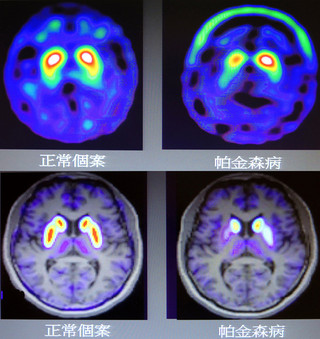

國內帕金森氏症研究獲選為頂尖學術期刊《自然回顧》6月號的研究焦點。林口長庚醫院團隊日前發表於《美國醫學會期刊:神經學》的研究,歷時5年多、分析逾300個臨床病例,透過「AV133正子影像」系統,突破過去帕...